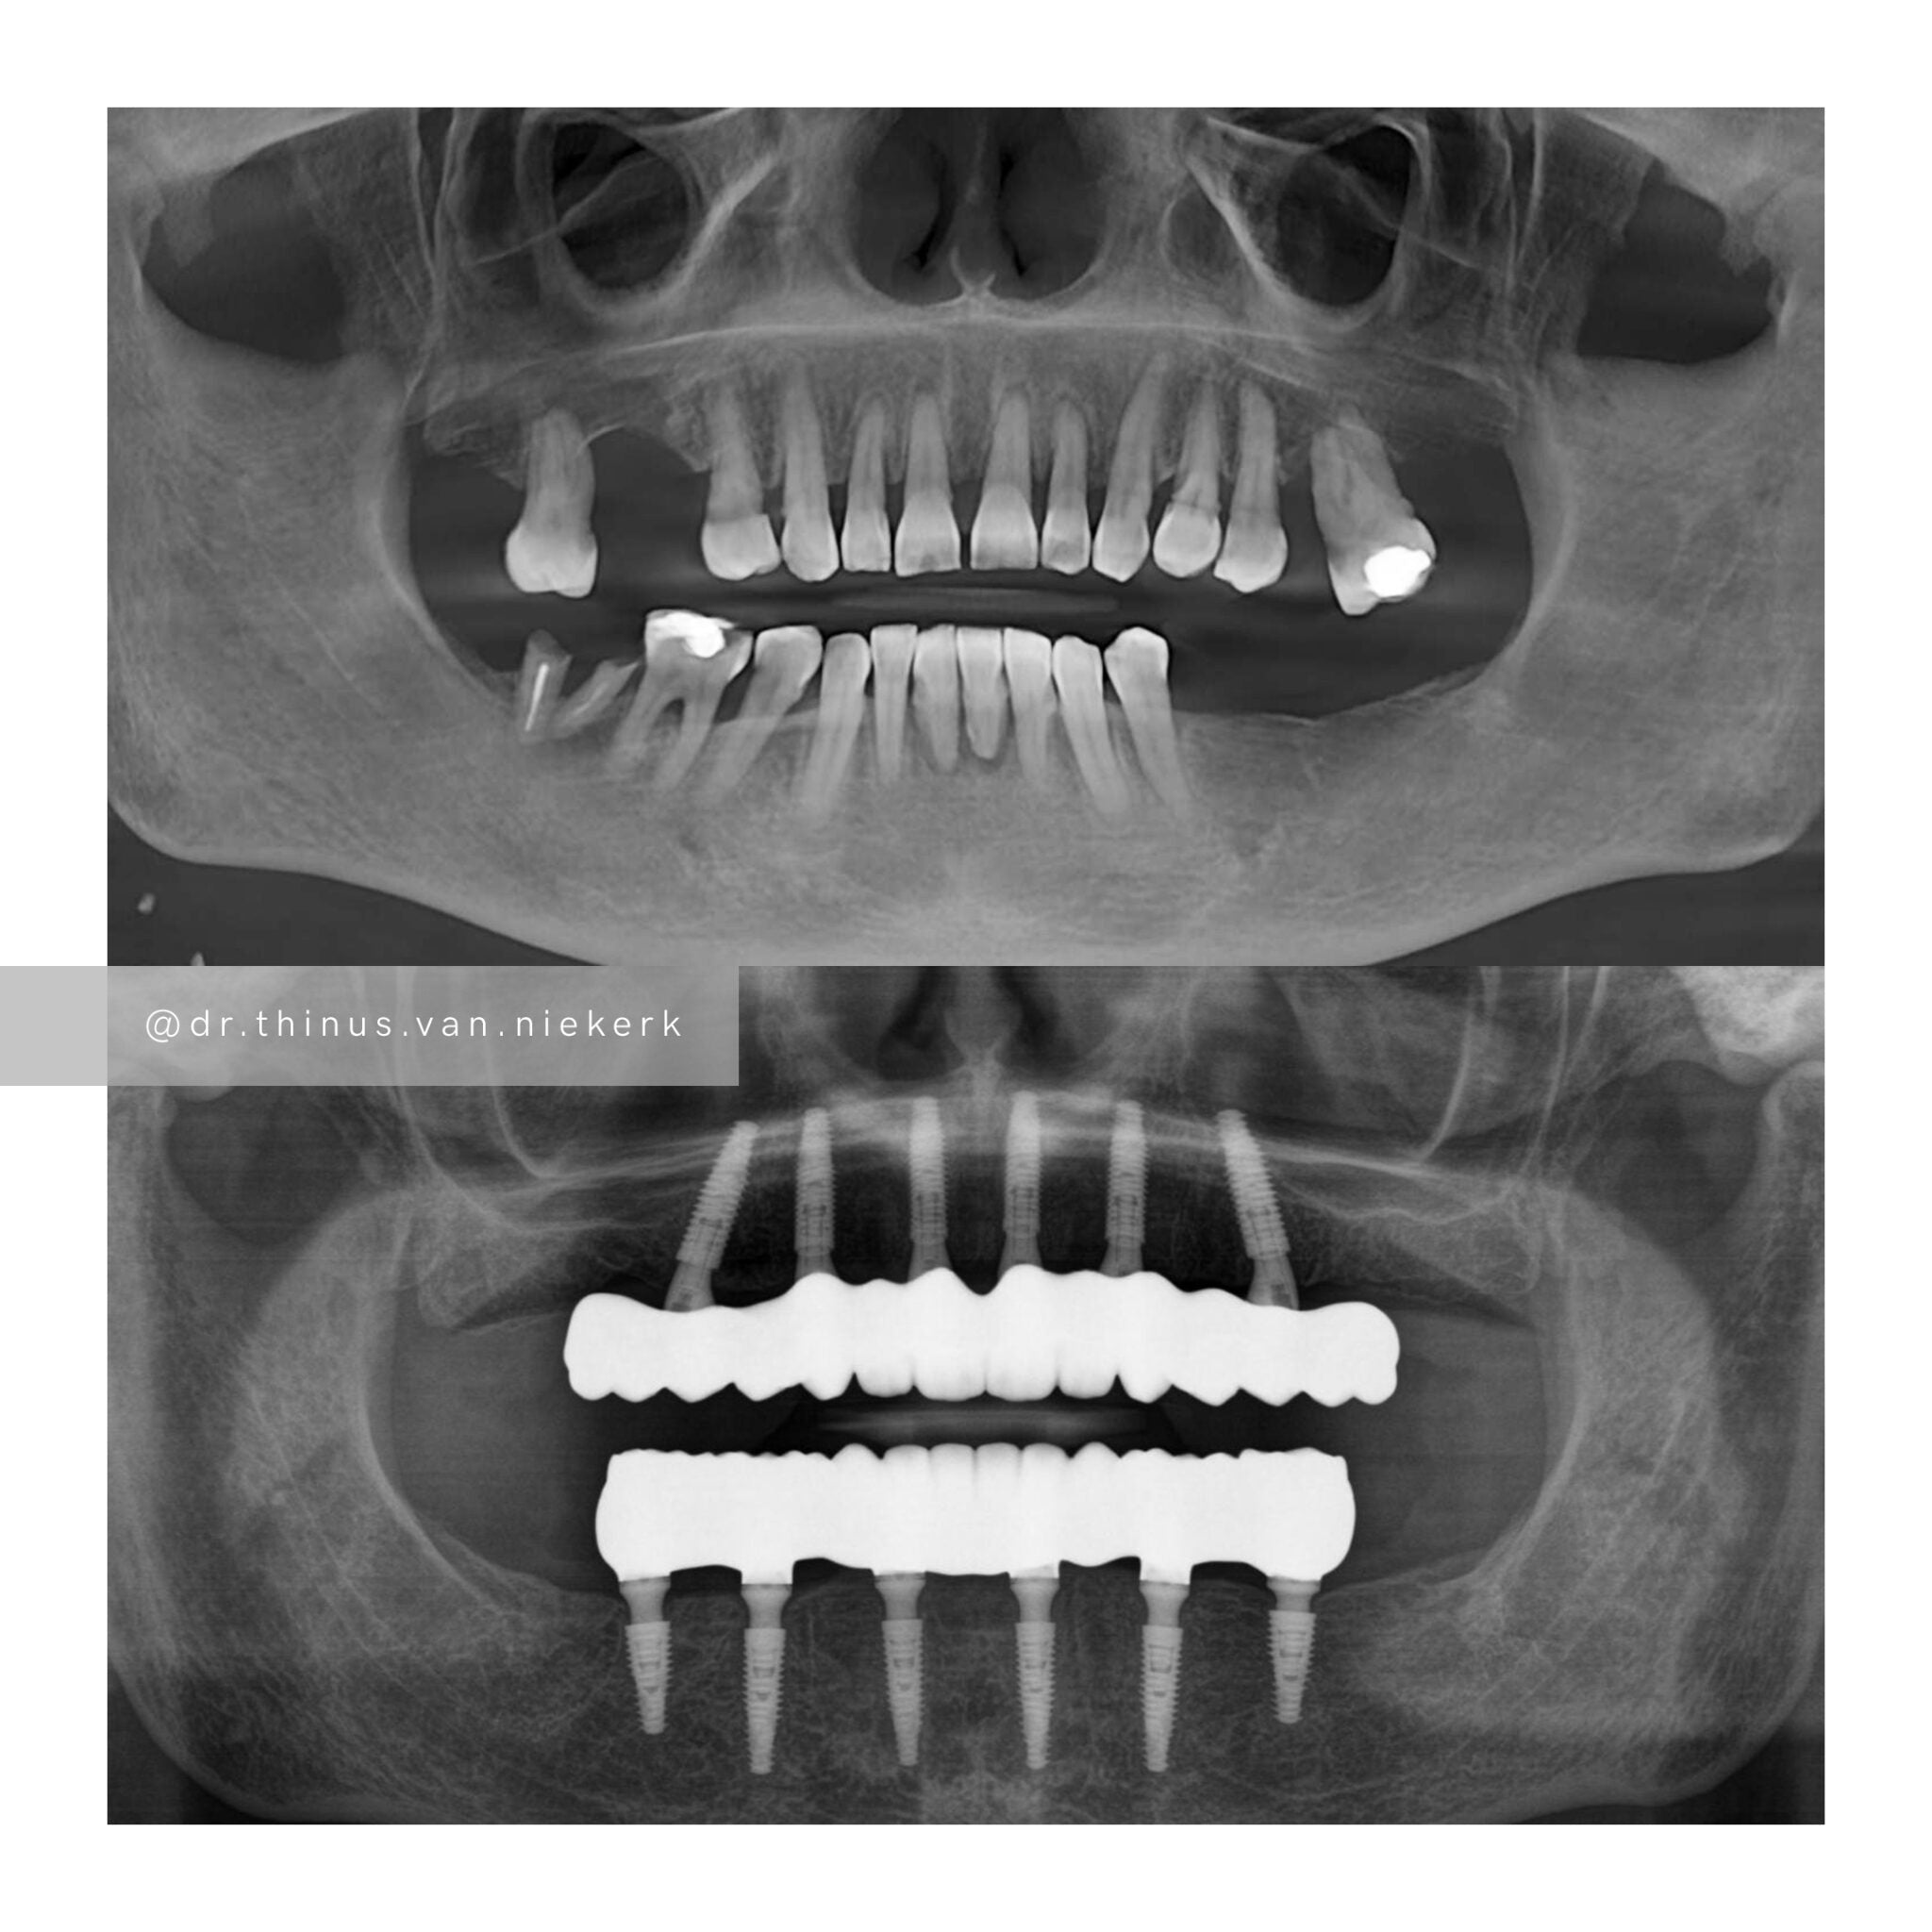

Our patient endured a long history of oral disease and associated infections. Our aim was to remove all elements of infection and disease and to restore function as quickly as possible. Six fully-guided implants were placed and immediately restored with implant-supported prosthesis in both the upper and lower jaws respectively. These were then converted to final zirconia framework prosthesis as healing and tissue remodeling allowed. The complete timeline for a treatment such as this varies from 6-24 months.

COMMENTS

This was a landmark case for our clinic – being the first fully digitally-planned upper and lower rehabilitation. This case demonstrated the power and effectiveness of digital implant-surgery planning and CAD design software. No adjustments were needed at the placement of the final lower prosthesis.